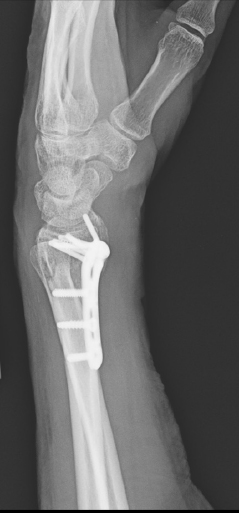

X-rays will be used to confirm the diagnosis. Fortunately, many of these fractures can be treated without surgery. Sometimes, the best thing is to push the fracture back into a better position and then hold it there with a cast. However, there are occasions where surgery is the best option. Surgery allows for the bones to be held in a better position more securely. With surgery, the bones can be held in place with pins, plates, and screws, and sometimes a combination of all of these. No matter the treatment, these fractures usually require at least 6 weeks to heal before it is ok to begin using the hand and wrist without restriction, but it often takes months before the pain and the stiffness fully resolve.

60-year-old female without other medical problems fell and landed primarily on her left hand and wrist. She had immediate pain and deformity at the wrist. She went to the emergency room where x-rays were performed showing her injury – a distal radius fracture. An attempt was made at improving the fracture position by the emergency room doctors and she was splinted. She was then referred to my clinic. She was seen soon afterwards. It was noted on new x-rays that the broken bone was in a less than ideal position. After a thorough discussion of the patient’s goals and concerns, surgery was felt to be the best option for her. Surgery was performed one week after her initial injury under general anesthesia. She was allowed to begin moving her wrist after her first post-operative visit 10 days after surgery and begin full weight bearing on the hand and wrist just under 6 weeks after surgery. She now has full function.